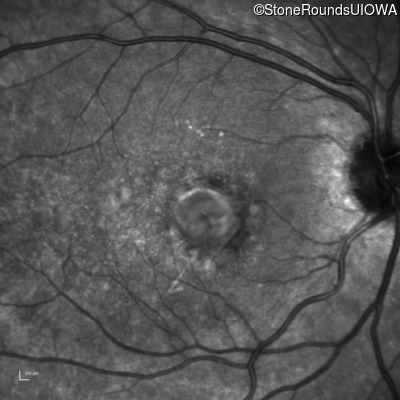

This 15 year old girl came to medical attention during a routine athletic vision screening when the acuity in her right eye was observed to be abnormal.

Age at visit: 19 years

Diagnosis & molecular findings

Best Disease BEST1 Asp228Glu GAC>GAG Asn259 ins2aacAA AR